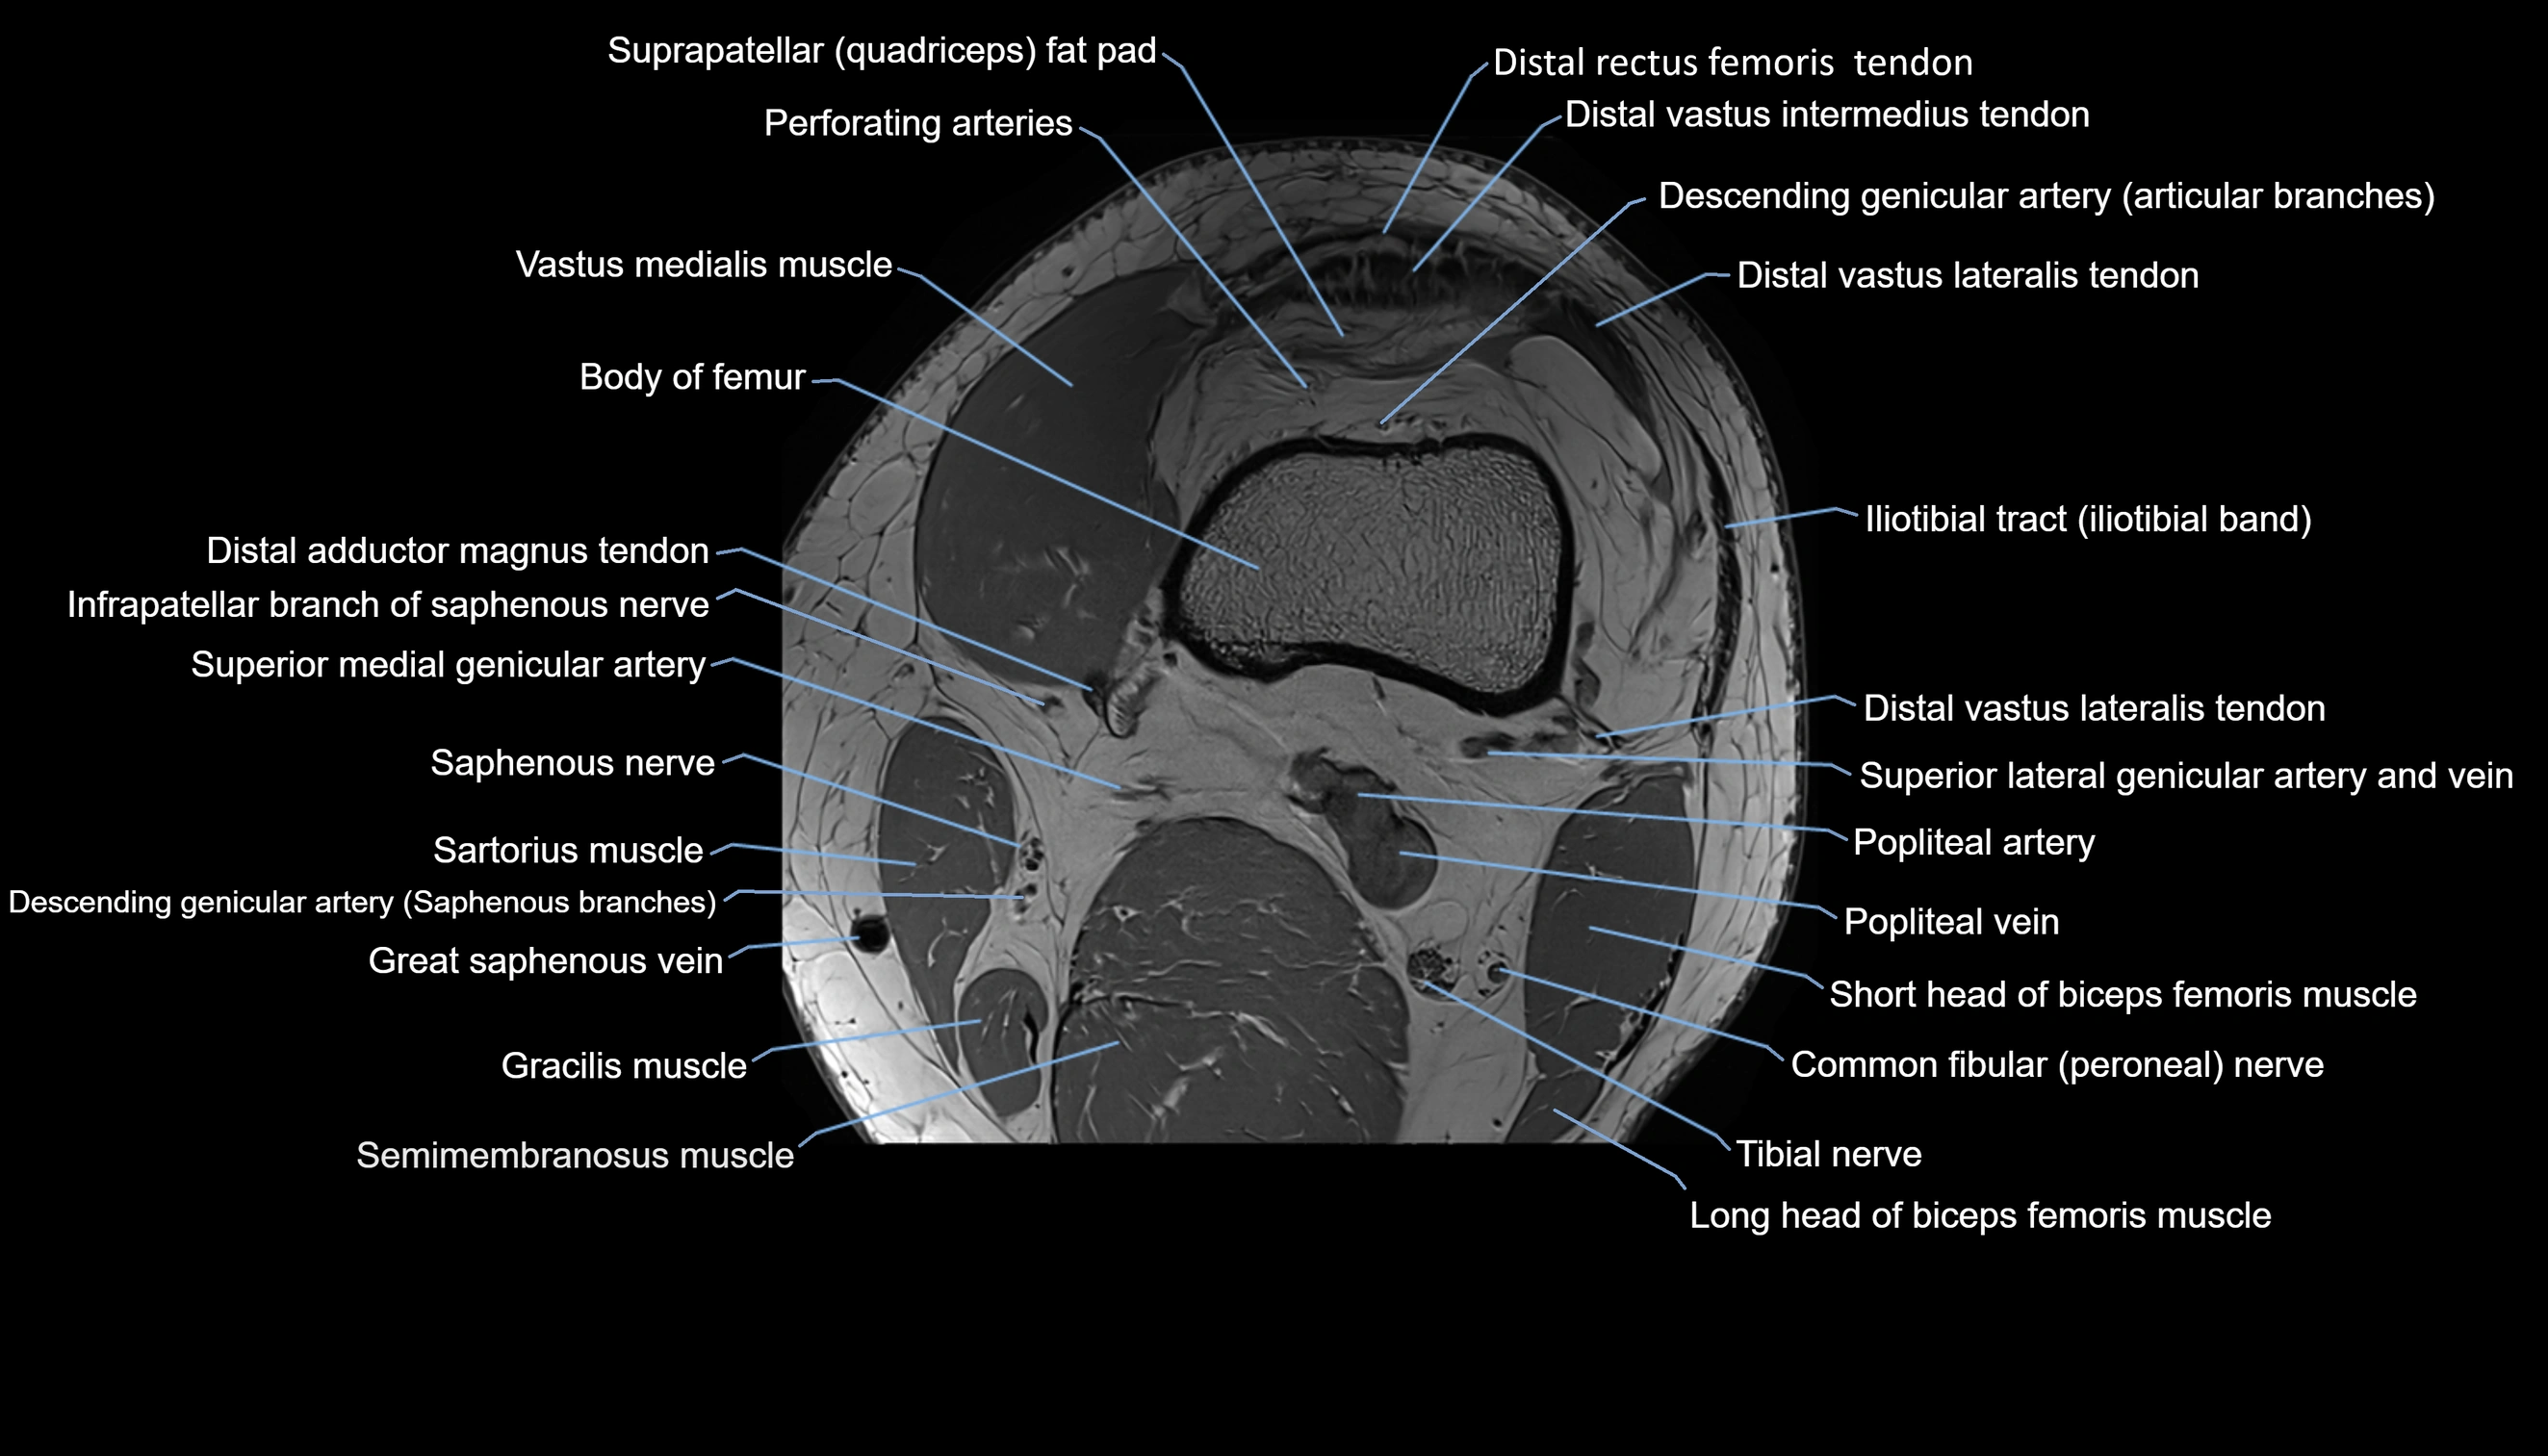

- Body of femur

- Perforating Arteries (Knee joint)

- Popliteal artery

- Popliteal vein

- Saphenous nerve

- Sartorius muscle

- Semimembranosus muscle

- Tibial nerve

- Vastus lateralis muscle

- Vastus medialis muscle

- great saphenous vein